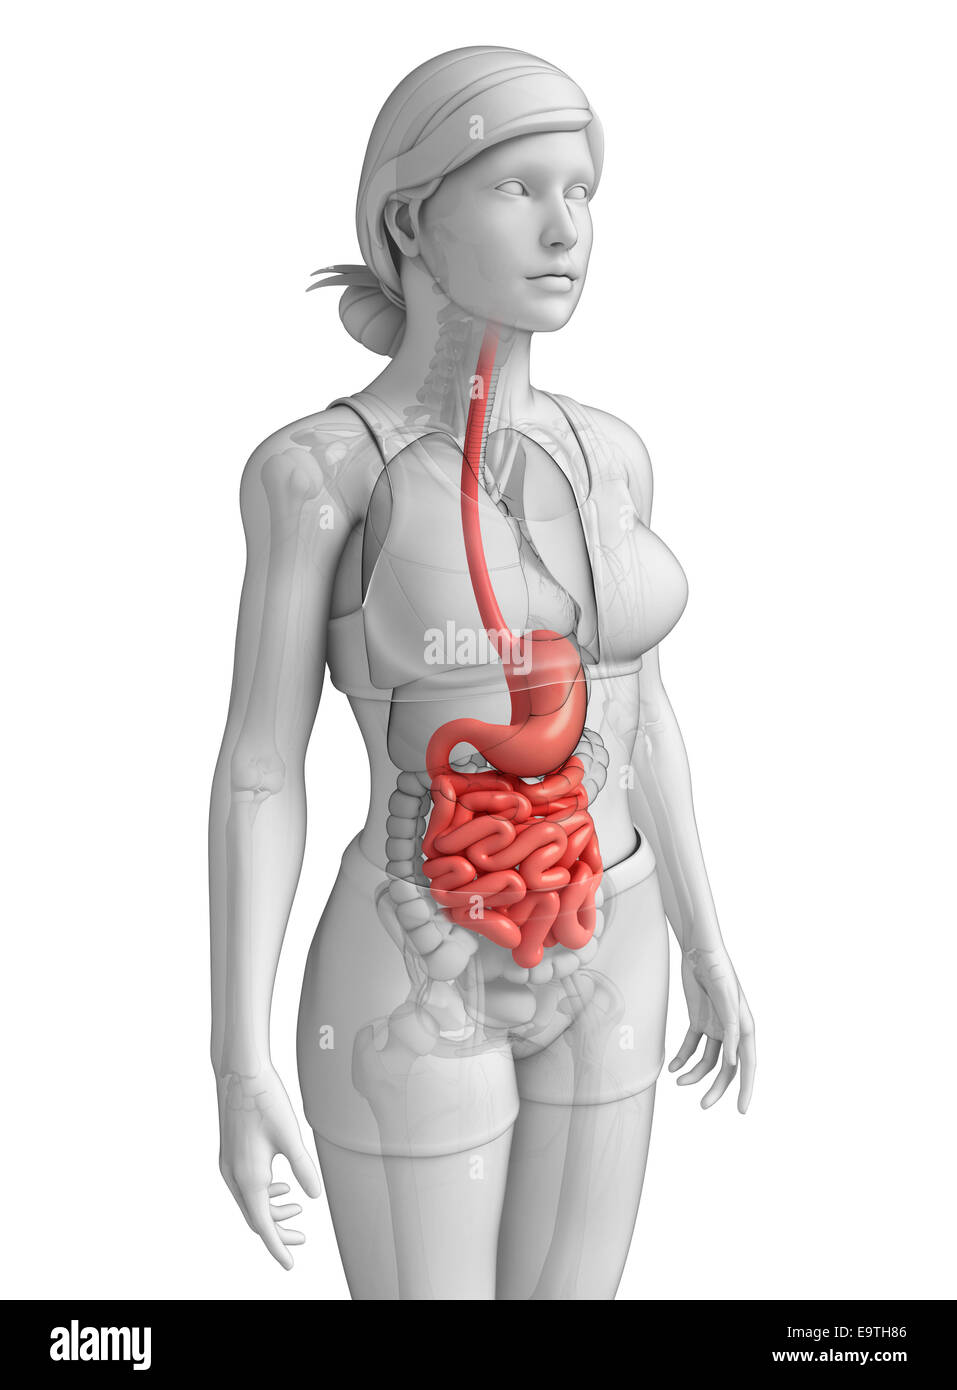

Illustration du petit intestin anatomie féminine Banque D'Imageshttps://www.alamyimages.fr/image-license-details/?v=1https://www.alamyimages.fr/photo-image-illustration-du-petit-intestin-anatomie-feminine-74913782.html

Illustration du petit intestin anatomie féminine Banque D'Imageshttps://www.alamyimages.fr/image-license-details/?v=1https://www.alamyimages.fr/photo-image-illustration-du-petit-intestin-anatomie-feminine-74913782.htmlRFE9TH86–Illustration du petit intestin anatomie féminine